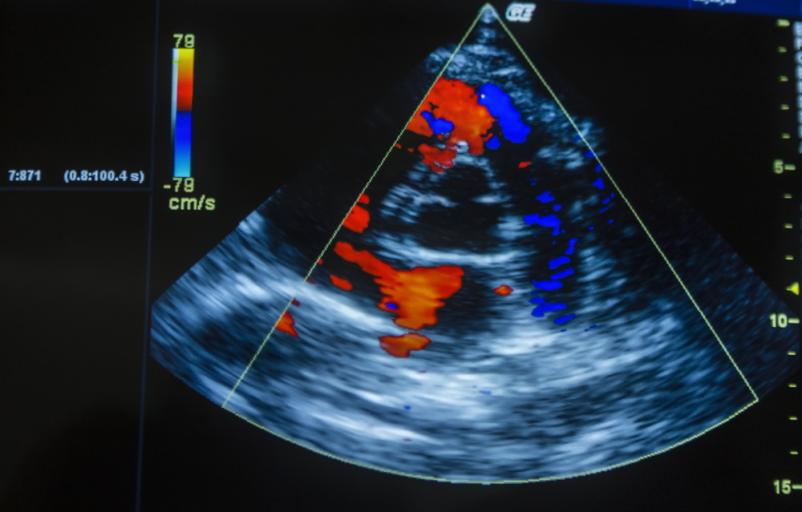

Ko gre za zdravje, si vsi želimo jasnih odgovorov in strokovnega pristopa. Prav zato je ultrazvok srca Ptuj ena izmed najbolj iskanih storitev pri KARDIOMED d.o.o., kjer strokovnost združujejo s prijaznostjo in sodobno tehnologijo. Pregled je popolnoma neinvaziven, izjemno informativen in idealen za vse, ki želijo preveriti delovanje svojega srca, preventivno ali zaradi že obstoječih težav.

V KARDIOMED d.o.o. se vsak pacient počuti varno in dobrodošlo. Ekipa z dolgoletnimi izkušnjami poskrbi, da je pregled prijeten, jasen in razumljiv, rezultati pa hitro na voljo. Ultrazvok srca Ptuj omogoča vpogled v delovanje zaklopk, črpalno funkcijo srca in morebitne nepravilnosti, ki jih pogosto ni mogoče zaznati z drugimi metodami.

- Transtorakalna ehokardiografija – podrobna analiza srčne anatomije.

Ultrazvok srca je povsem neboleč in neinvaziven pregled. Med preiskavo pacient leži na boku, zdravnik pa s sondo opravi posnetke srca. Pregled običajno traja 20–30 minut, rezultati pa so na voljo hitro. Posebne priprave niso potrebne.